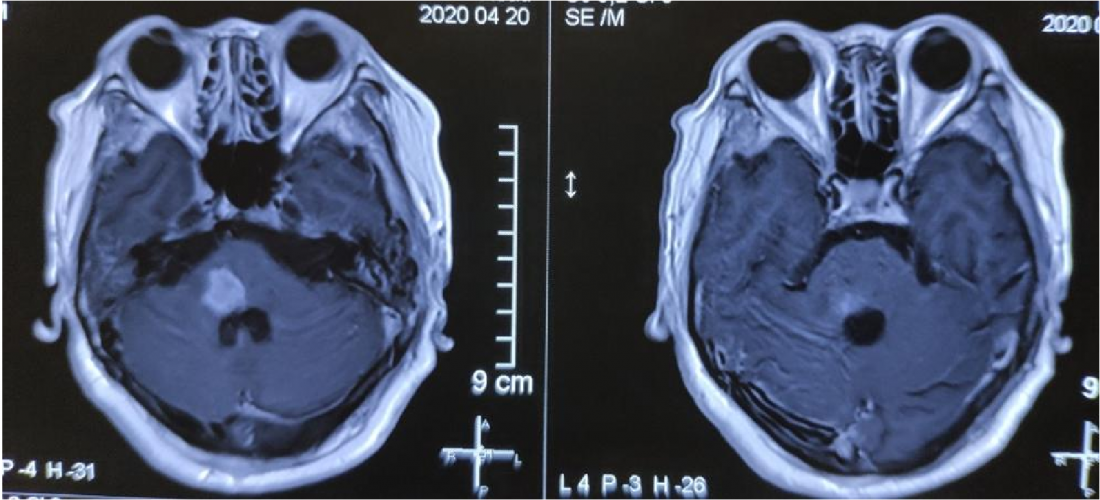

MR显示桥脑右侧高信号影,肿瘤位于四脑室界沟上方之桥脑部分,邻近面丘及动眼神经核,因此患者出现面瘫。

肿瘤位于桥脑与延髓交界处

面神经丘受压明显

术后MR: